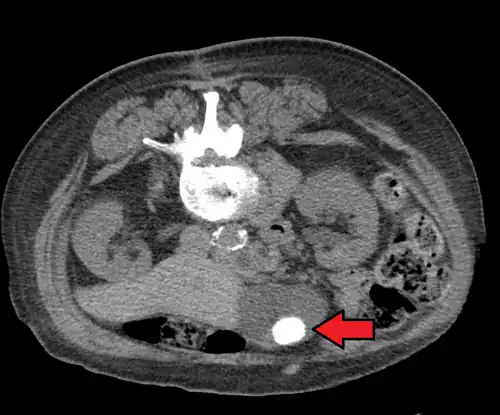

Gallstones as seen on plain X-ray

-

Large gallstone as seen on CT -